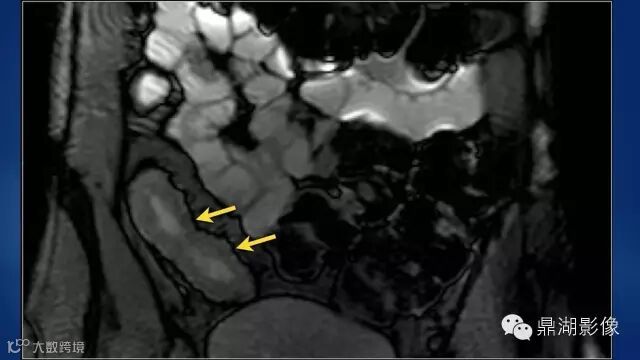

what's the meaning of fat halo sign?

粘膜下水肿或脂肪沉积,可致肠壁内呈低密度层(halo征),其最初用来描述溃疡性结肠炎,是良性肠道病变的结果,无特异性,也可存在于放射性肠炎,移植-受体疾病和慢性缺血性肠炎以及单性的肥胖症患者。

Fat halo aslo can be seen in normal terminal ileum.